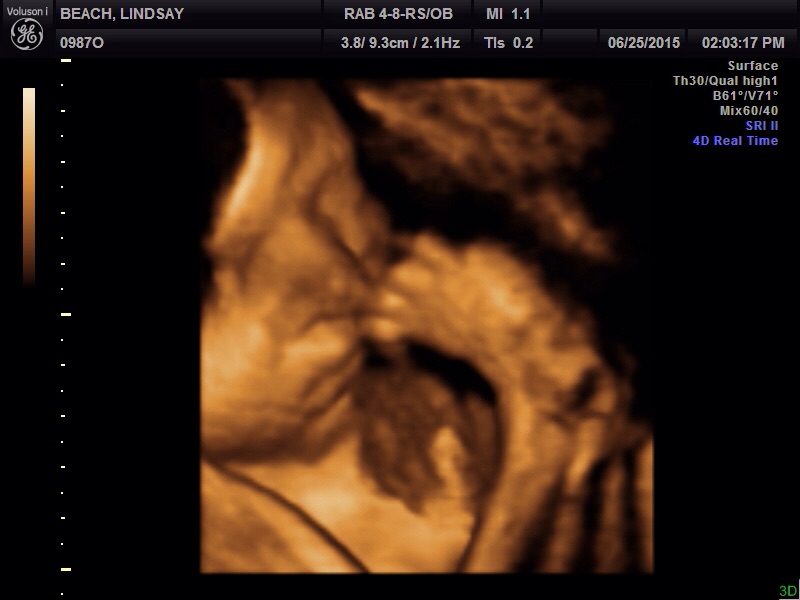

• We did one for our anniversary because we thought it would be something fun to do and it was amazing. Ours was 3D with HD live (something about showing skin elasticity... I don't know much about it). Here are some pictures from 29 weeks. We actually also got a video and could see him moving his little thumb into his mouth.